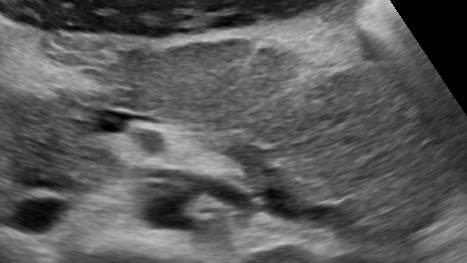

Реактивный панкреатит у ребёнка (УЗИ)